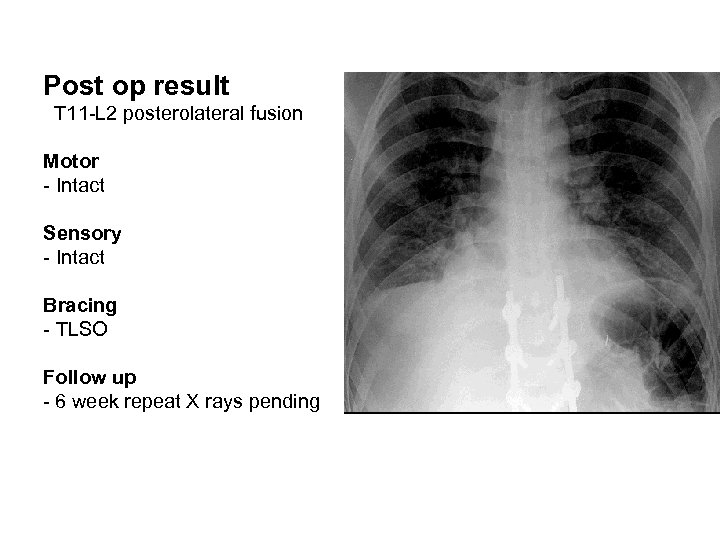

Post op result T 11 -L 2 posterolateral fusion Motor - Intact Sensory - Intact Bracing - TLSO Follow up - 6 week repeat X rays pending